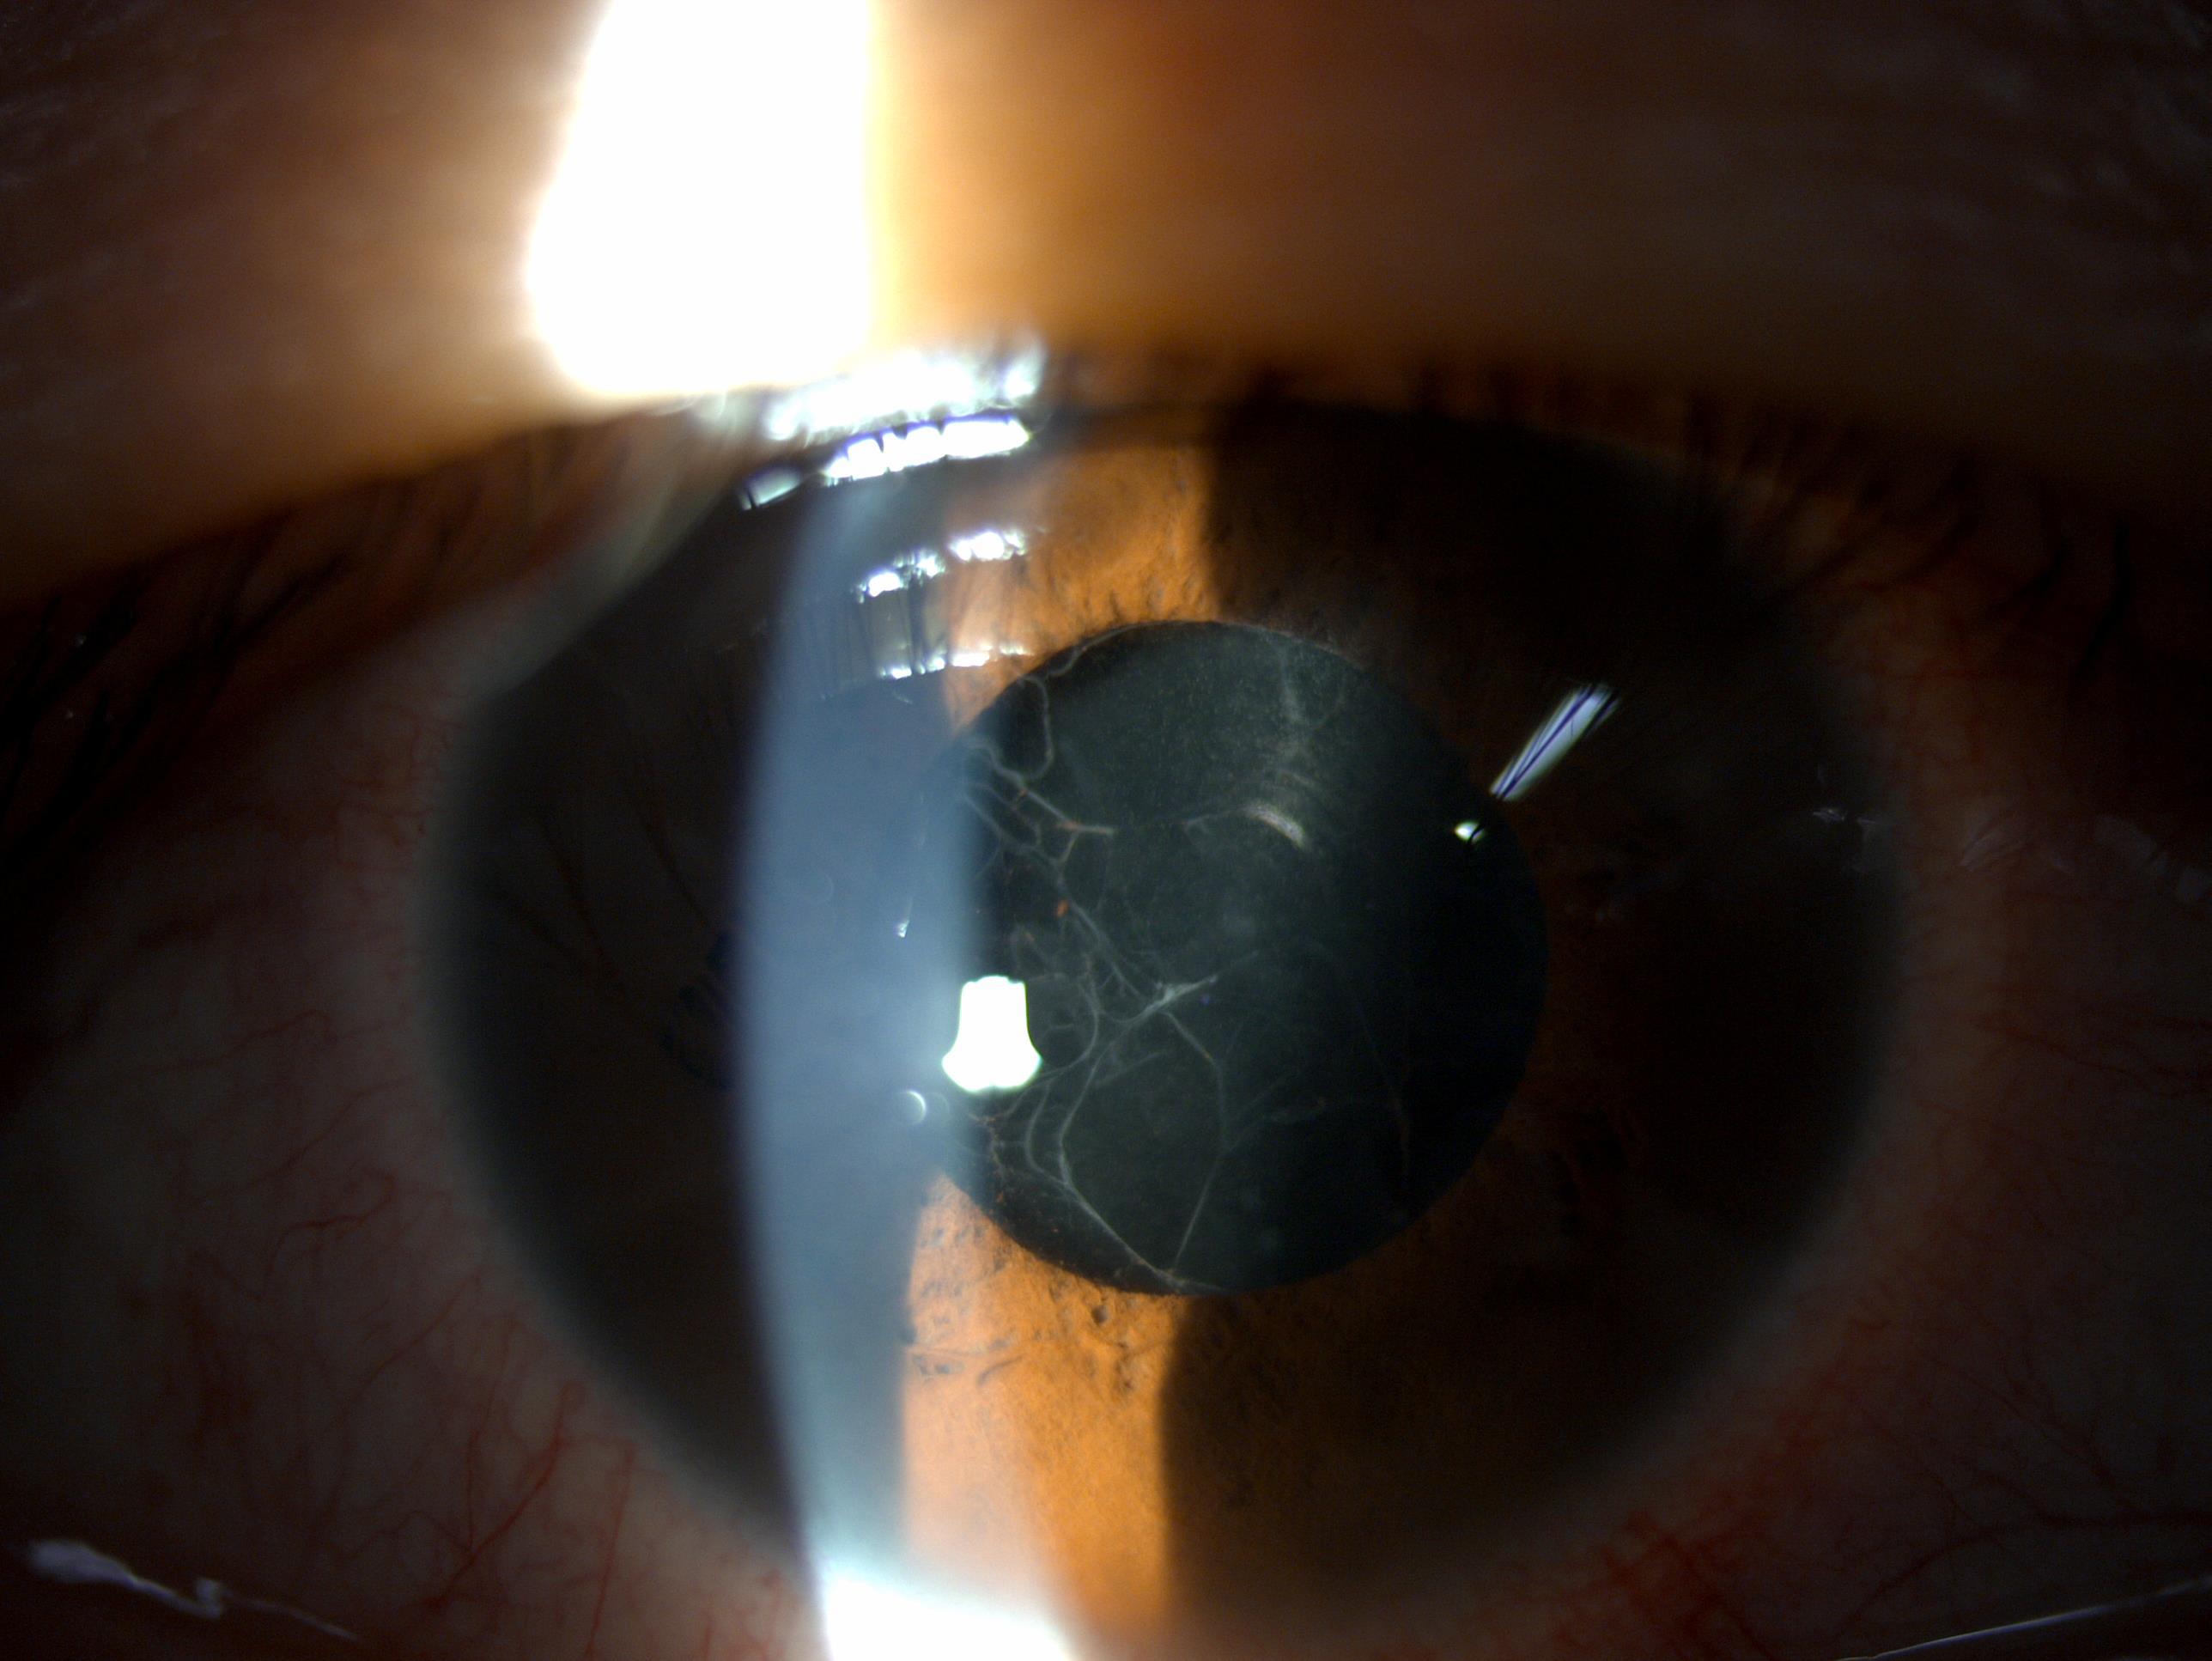

他们8:55到了医院以后立刻做了相关检查,我差不多9点多也到了医院。等他检查完以后到我诊室一看,矫正视力只有0.15,轻度充血,角膜轻度水肿,房水轻度混浊,前房和瞳孔区有明显的渗出物,眼底模糊不清。我马上问他,这两天有没有洗澡,他说昨天下午洗澡了,但是洗澡时手术过的眼睛用毛巾保护住了,确认没有进水。我结合了相关的客观检查认为主要还是眼前段的炎症反应,当时就判断很大可能是一个非感染性的炎症反应,但是也不能完全排除感染性眼内炎。先紧急处理观察三个小时左右再根据病情变化决定下一步的治疗措施等。